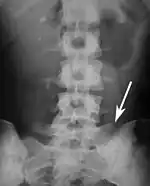

Lumbarization of sacral vertebra 1, seen as 6 vertebrae that do not connect to ribs.

Sacralization of the L5 vertebra is seen at the lower right of the image.